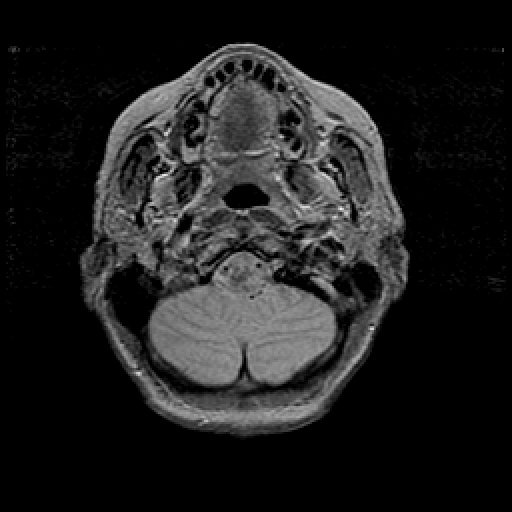

Proton density-weighted structural MR: Slice 7

Slice 7